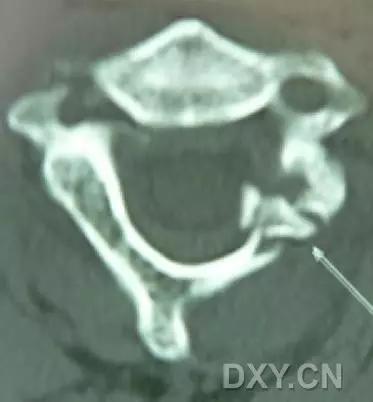

6. Jefferson 骨折

寰椎环的压缩性骨折,骨折是由枢椎压缩性外力引起,骨折多发生在寰椎前侧后侧以及侧方小关节。

第一颈椎双侧性前、后弓骨折,X 线片上很难发现骨折线,有时在正位片上看到 C1 关节突双侧性向外移位,侧位片上看到寰椎前后径增宽及椎前软组织肿胀阴影,CT 检查最为清楚,而 MRI 检查智能显示脊髓损伤情况。

A 图是稳定的 Jefferson 骨折(横韧带完整)轴位像。B 图是不稳定的 Jefferson 骨折(横韧带撕裂)轴位像